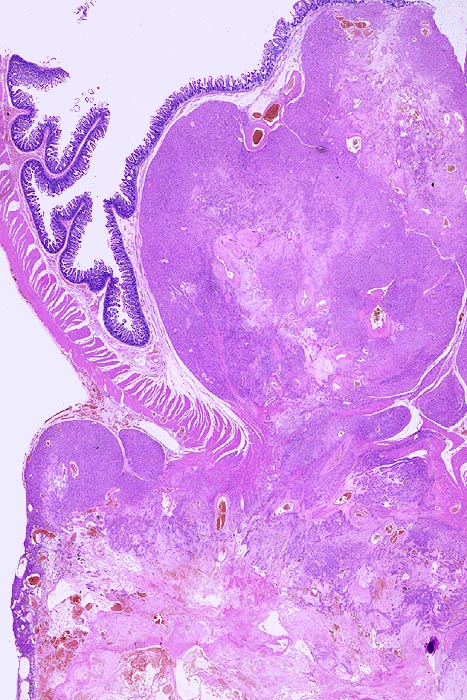

• Scharf begrenzter kugeliger Tumor in der Submukosa des Magenantrums

• Über dem Tumor entzündungsfreie Antrumschleimhaut mit partiell reepithelialisiertem oberflächlichem Ulkus (Quellungsfibrinoid).

• Der Tumor besteht aus längs und quer getroffenen Faszikeln spindelförmiger Tumorzellen, welche an glatte Muskelzellen oder Schwannzellen erinnern.

• Herdförmig pseudozystische Auflockerung des Tumorgewebes.